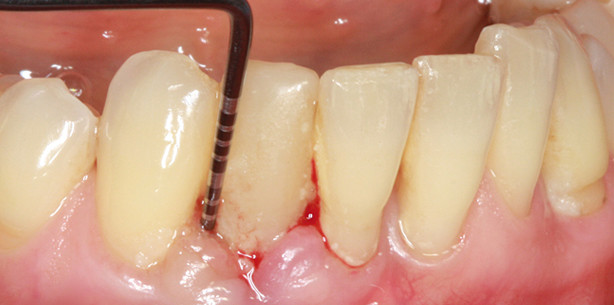

Pulverstrahlgeräte sind bereits seit vielen Jahren im Rahmen der supragingivalen Anwendung, insbesondere bei der professionellen Zahnreinigung, erfolgreich im Einsatz. Die Indikationserweiterung auf subgingivale mit Biofilm belastete Oberflächen wurde mithilfe eines nur wenig abrasiven Glyzin-Pulvers (z.B. Air-Flow powder Perio, EMS) und speziellen Applikatoren möglich (siehe Abb. 1–5). Die Reinigungs- beziehungsweise Dekontaminationswirkung an Implantatoberflächen dieser (circa 20 µm großen) aus der Aminosäure Glyzin bestehenden Kristalle ist erheblich besser im Vergleich zu konventionellen Handinstrumenten und Ultraschallscalern.25–28 Darüber hinaus konnte gezeigt werden, dass das Glyzin-Pulver im Rahmen des Strahlverfahrens keine nachteiligen Effekte auf das umgebende Weichgewebe ausübte. Im Vergleich hierzu führten konventionelle Handinstrumente zu einer erheblichen Traumatisierung der angrenzenden Weichgewebe.22, 29

Die Entwicklung neuer Instrumentenansätze insbesondere für die geschlossene Parodontitis- und Periimplantitistherapie (Perio-Flow Handstück für Air-Flow Master, EMS) ermöglicht nunmehr eine effektive und effiziente Reinigung der Zahn- und Implantatoberfläche bei ­einer weitestgehend atraumatischen, geschlossenen Vorgehensweise.9, 22, 28 Die Therapiemethode ermöglicht eine drei- bis fünfmal kürzere Behandlungsdauer mit wesentlich weniger Schmerzen, verglichen mit konventionellen Handinstrumenten.9 Allerdings kann auch mit der niedrigabrasiven Pulverstrahltechnik keine anhaltende Keimreduktion erreicht werden. Neben der rein physikalisch-mechanischen Bearbeitung der Implantatoberflächen werden auch chemische Verfahren zur Desinfektion der biofilmbesiedelten Implantat- oder Zahnoberflächen eingesetzt.